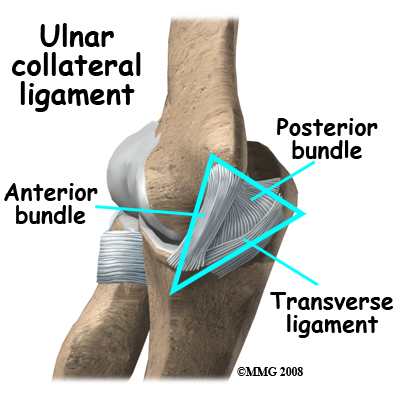

In the elbow, two of the most important ligaments are the ulnar collateral ligament (UCL) and the lateral collateral ligament. The UCL is also known as the medial collateral ligament. The ulnar collateral ligament is on the medial (the side of the elbow that's next to the body) side of the elbow and the lateral collateral is on the outside. The ulnar collateral ligament is a thick band of ligamentous tissue that forms a triangular shape along the medial elbow. It has an anterior bundle, posterior bundle, and a thinner, transverse ligament.

Together these two ligaments, the ulnar (or medial) collateral and the lateral collateral, connect the humerus to the ulna and keep it tightly in place as it slides through the groove at the end of the humerus. These ligaments are the main source of stability for the elbow. They can be torn when there is an injury or dislocation of the elbow. If they do not heal correctly the elbow can be too loose or unstable. The ulnar collateral ligament can also be damaged by overuse and repetitive stress, such as the throwing motion.